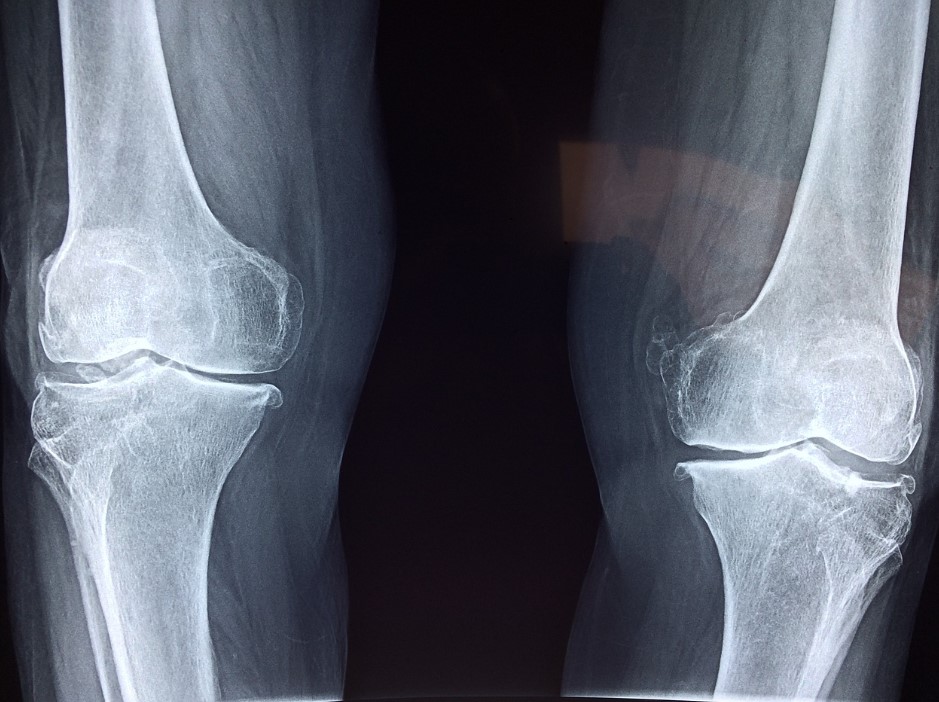

무릎 통증은 무릎 관절이 안 좋을 때 가장 흔하게 나타나는 증상입니다. 무릎 통증은 무릎을 움직일 때, 특히 계단을 오르거나 내릴 때, 무릎을 꿇을 때 심해집니다. 무릎 통증은 무릎 관절의 염증이나 손상으로 인해 발생합니다. 무릎 통증이 심한 경우, 무릎을 움직일 수 없을 수도 있습니다.

무릎 삐걱거리거나 딱딱 소리는 무릎 관절을 움직일 때, 뼈와 뼈가 마찰되어 소리가 나는 증상입니다. 무릎 삐걱거리는 소리는 무릎 관절의 염증이나 손상으로 인해 발생합니다. 무릎 삐걱거리는 소리가 심한 경우, 무릎을 움직일 수 없을 수도 있습니다.